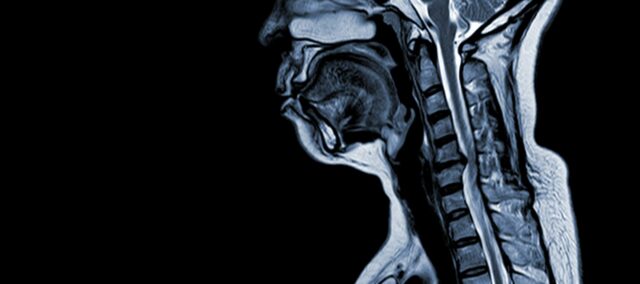

Cervikalna spondilotična mielopatija (CSM) je nevrološko stanje, ki je glavni vzrok za poškodbo hrbtenjače pri odraslih. Preprosto povedano, gre za stiskanje ali poškodbo hrbtenjače v vratu, predvsem zaradi naravnega procesa staranja, ki prizadene vratna vretenca. Izraz "mielopatija" izhaja iz grških besed "myelon", ki pomeni "hrbtenjača", in "pathos", ki pomeni "bolezen".

Patofiziologija

- Degeneracija diska (izboklina diska): CSM se pogosto začne z degeneracijo medvretenčnih ploščic v vratni hrbtenici, ki se izbočijo ali izbočijo v hrbtenični kanal.

- Subperiostalna tvorba kosti (ventralno od hrbteničnega kanala): Zaradi povečane mehanske obremenitve telo tvori novo kostno tkivo na sprednji (ventralni) strani hrbteničnega kanala, kar lahko zoži prostor za hrbtenjačo.

- Osifikacija zadnje vzdolžne vezi: Zadnja vzdolžna vez se lahko okostene, strdi in kalcificira, kar prispeva k zožitvi hrbteničnega kanala.

- Hipertrofija ligamentum flavum: Zaradi hipertrofije ligamentum flavum se zgosti in postane manj prožen, kar še dodatno posega v prostor znotraj hrbteničnega kanala in stiska hrbtenjačo.

Te strukturne spremembe skupaj vodijo v kompresijo in zožitev hrbteničnega kanala, kar povzroči značilne simptome in zaplete, povezane s CSM. Prepoznavanje teh dejavnikov tveganja in razumevanje vključenih patofizioloških mehanizmov je bistveno za preprečevanje in zdravljenje. Zgodnja diagnoza in ustrezni ukrepi so ključnega pomena za ublažitev posledic teh strukturnih sprememb na hrbtenjači.